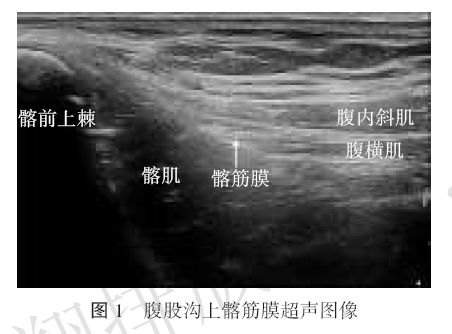

髂筋膜阻滞超声图

髂筋膜阻滞超声图,髂筋膜间隙阻滞

髂筋膜间隙阻滞

髂筋膜的解剖结构

髂筋膜间隙解剖

髂筋膜阻滞解剖图

髂筋膜解剖

髂筋膜阻滞体表定位

髂筋膜的解剖位置

髂筋膜

超声引导下髂筋膜阻滞

髂筋膜阻滞